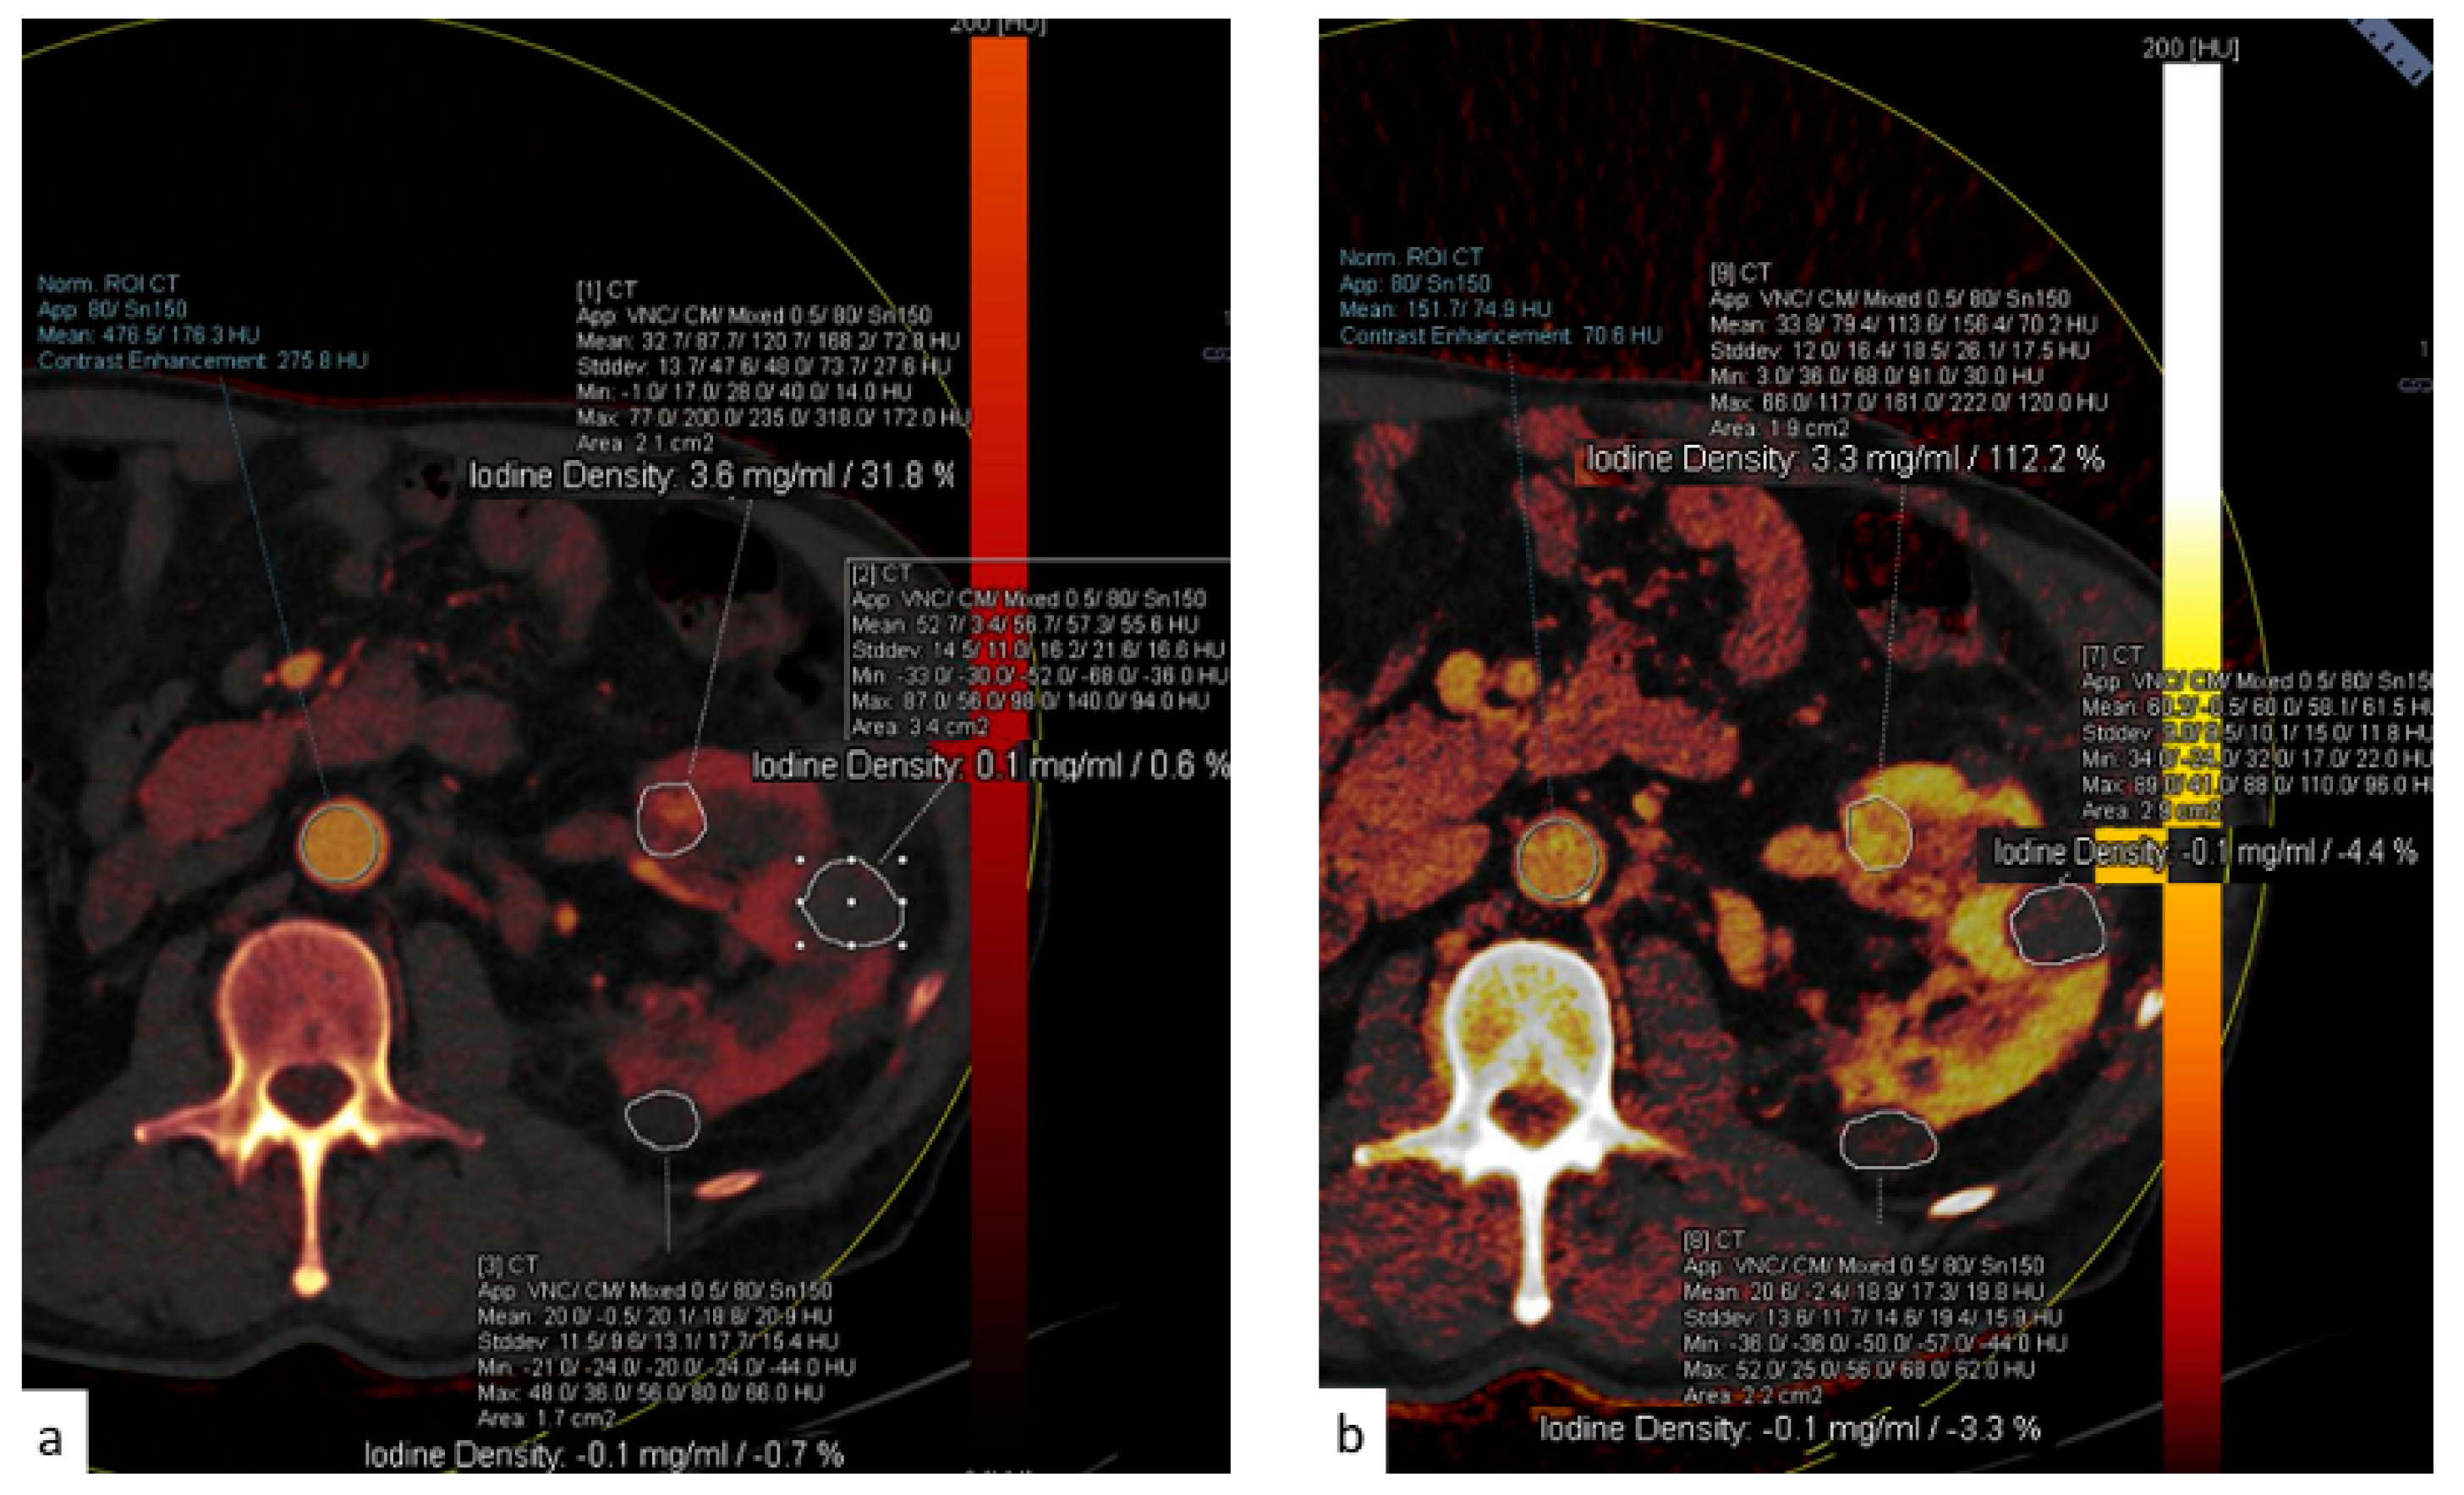

DECT images can also be post-processed to create maps that show the concentration of different components including iodine, fat, and calcium. The construction of iodine maps aids in the identification of tissues with higher or lower iodine concentrations (Figure 10, Figure 11 and Figure 12).

Figure 10.

(a) Dual-energy acquisition of a corticomedullary phase with visualization of the iodine map. (b) The posterior and external renal components do not show iodine contents, whereas the anterior nodulation shows clear iodine content.

Iodine density measurements have different applications. First, they enable the management of incidentally detected renal masses, allowing their characterization from a single examination and avoiding additional imaging and diagnostic timing delays [73]. Virtual monochromatic images demonstrated better correction of beam hardening artifacts, reducing the degree of pseudo-enhancement in intraparenchymal renal cysts, and allowing for a more confident diagnosis, when compared to standard CT acquisitions [74].

Iodine density measurements and iodine overlay images provide a visual depiction of enhancement that helps in the discrimination between avidly enhancing clear cell renal cell carcinoma and hypoenhancing papillary renal cell carcinoma [75] and is also particularly useful in the assessment of treatment response when using targeted antiangiogenic agents for clear cell renal cell carcinoma [76] and in patients treated with ablation [77].